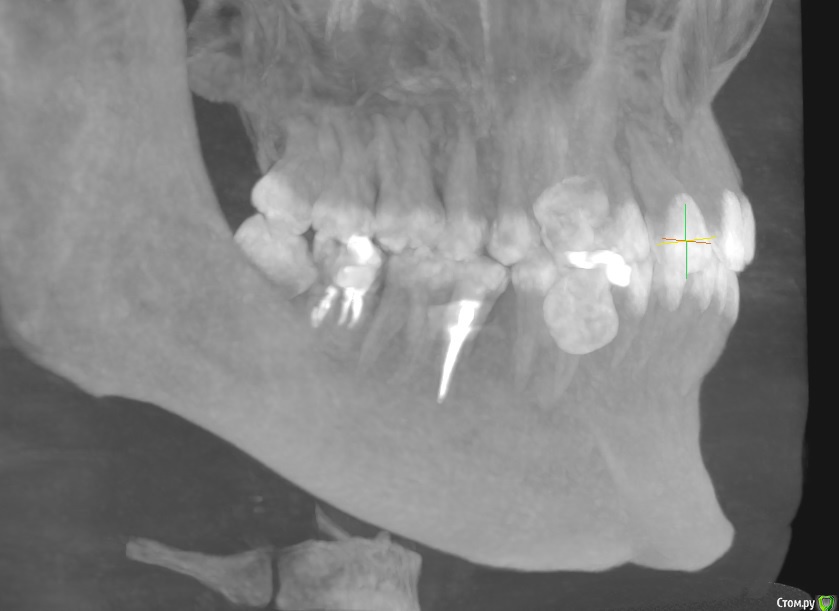

Boris87 Опубликовано 21 марта, 2020 Поделиться Опубликовано 21 марта, 2020 (изменено) Здравствуйте. В 2008 г. нижняя семёрка была депульпирована. Не беспокоит, но откололся небольшой край зуба (года 2 назад уже), и вокруг пломбы уже кариес. Иногда когда ем из того места чувствуется неприятный привкус. Рядом на восьмёрке небольшой кариес, и она упирается в край 7-го. Походил по клиникам. Одни говорят - восьмёрку удалять, на семёрку коронку. Другие - что и семёрку удалять. Ещё в одной сказали что восьмёрку даже можно оставить, пролечив кариес, и обточив семёрку чтобы ей не мешала + коронку, но другие говорили что так никто не обтачивает. В одной клинике говорили что могут просто нарастить светоотвержд. материалом. Я конечно хотел бы этого. Коронку не хочется (читал что металл в организме у многих потом проблемы вызывает, даже рак, особенно если никель в составе). А полностью диоксид циркония дорого, и не уверен что оправданно (зуб потом наверное всё равно удалять). Как тут лучше поступить? ЗЫ. ОПТГ делал в октябре, после этого 5-й зуб был пролечен, а КТ - недавно. Изменено 21 марта, 2020 пользователем Boris87 Ссылка на комментарий

red_butler Опубликовано 21 марта, 2020 Поделиться Опубликовано 21 марта, 2020 Восьмой удалять, седьмой убрать пломбу и кариес и принимать решение, но на фото прогноз седьмого зуба плохой 1 Ссылка на комментарий

DmitrySH Опубликовано 21 марта, 2020 Поделиться Опубликовано 21 марта, 2020 Восьмой удалять, седьмой убрать пломбу и кариес и принимать решение, но на фото прогноз седьмого зуба плохойСогласен. По фото мало понятно. Ссылка на комментарий